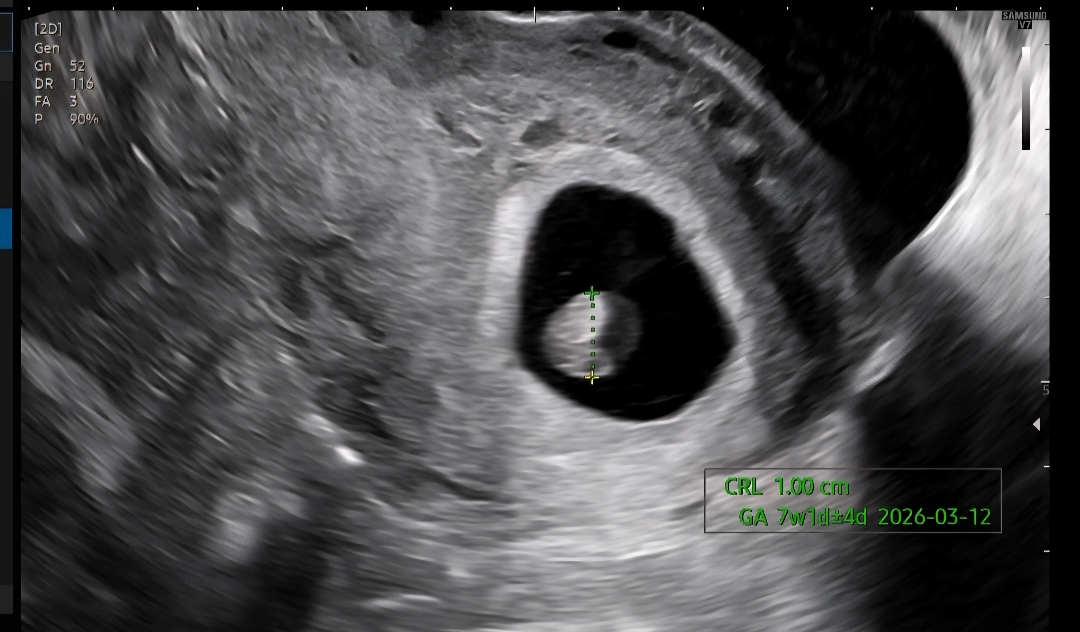

7주차 아기가 부은것같다고하는데

초음파 한참 보더니 아기가 부은것같다고 일시적인건지 문제가 있는건지 일주일 뒤에 보자고하셨어요 원래는 해당 의사선생님이 손바꿔서 다른 의사선생님께 또 확인을 해보려고했는데 다들 안계셔서 다른분한테는 진료를 못봤어요 이런 경우 겪어 보신적있나요?

아기가 진짜 부은거 같네요...큰병원 가보셔야할거같아요 원래 아가가 펼쳐져있는게 정상이거든요,,